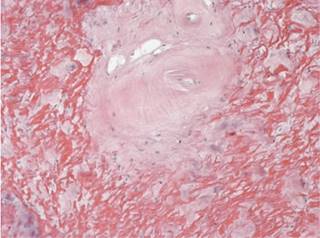

Figure 5: In the ligament flavum there are acellular basophilic amorphous nodular zones, which give them a hyalinized appearance.